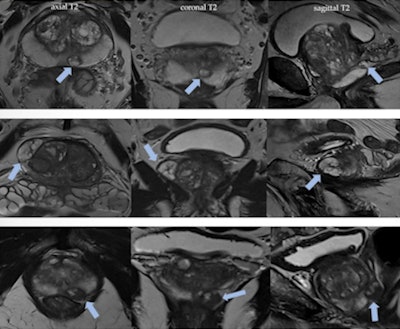

Benign prostatic hyperplasia nodules in the peripheral zone may mimic prostate cancer. Nodules with typically glandular type hyperplasia may appear in peripheral zone as ectopic or herniated nodules from the transition zone. It is important to analyze the morphology on T2-weighted imaging; look out for well-defined, rounded, encapsulated lesions; and identify the hyperintense component corresponding to hyperplastic glands with cystic ectasia. Figures courtesy of Dr. Daniel Vas et al and presented at ECR 2023.Also vital is a sound knowledge of the basic concepts of the Prostate MRI for Local Recurrence Reporting (PI-RR) after radiation therapy and radical prostatectomy and the Prostate Cancer Radiological Estimation of Change in Sequential Evaluation (PRECISE) scoring system in men on active surveillance for prostate cancer, they reported.

A 69-year-old man with urinary retention and recurrent prostatitis with chronic urinary catheter had a PSA of 3.79 ng/ml. MpMRI shows round, high signal intensity lesion on T2-weighted imaging in the right transitional zone (arrows), highlighting markedly restricted diffusion and "ring" peripheral contrast uptake, consistent with a small abscess. A lenticular area is visualized in the right peripheral zone (arrowheads), showing characteristics of a PI-RADS 4 lesion (restricted diffusion and low T2 signal intensity, contrast uptake). However, malignancy was suspected due to mpMRI, and taking into account the accompanying findings, it was thought this might correspond to a phlegmonous area (prostatitis).With larger collections, transrectal drainage can be useful to help resolution and patient recovery. "It is recommended to carry out follow-up MRI of a suspicious lesion detected during acute prostatitis with abscesses if it is not examined by biopsy," they noted.